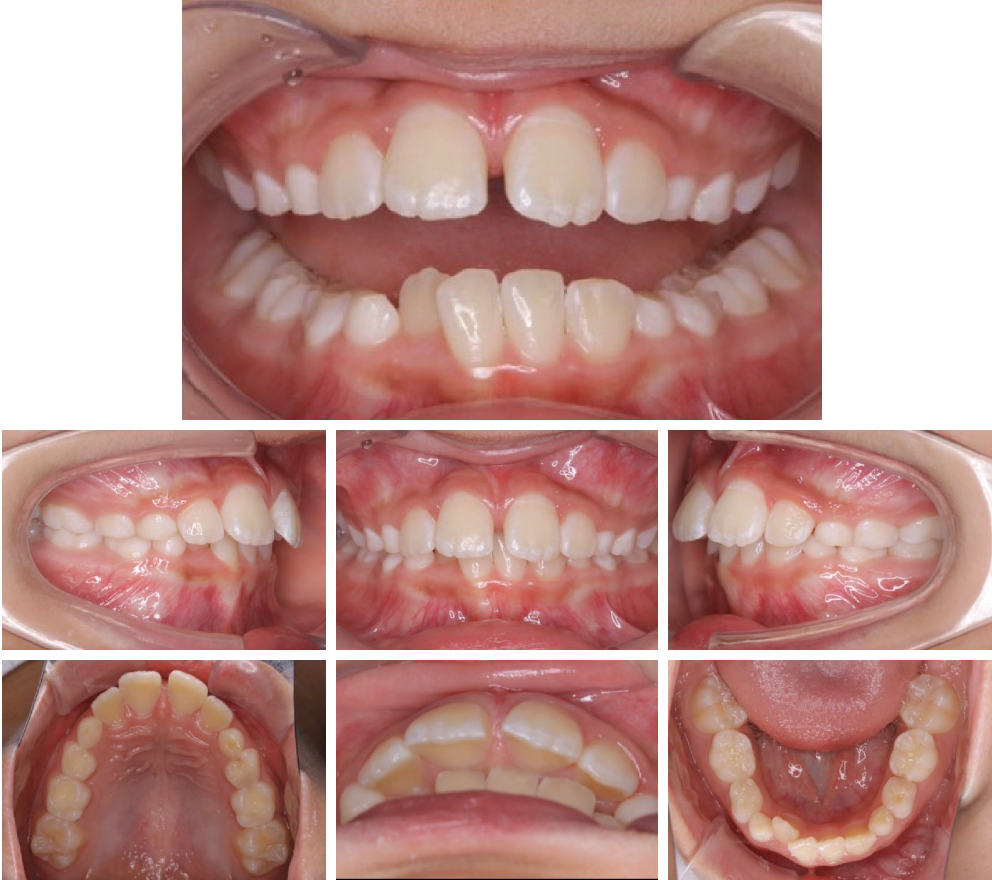

当院の症例

CASE